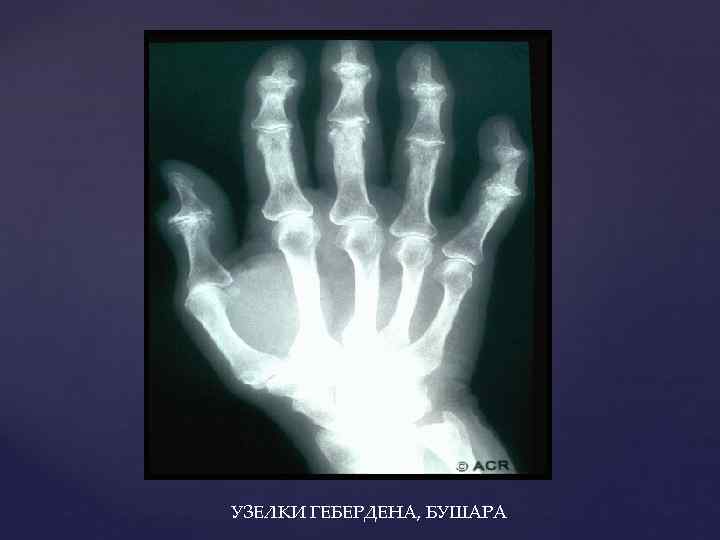

УЗЕЛКИ ГЕБЕРДЕНА, БУШАРА

УЗЕЛКИ ГЕБЕРДЕНА, БУШАРА

ОА КИСТЕЙ ДИСТАЛЬНЫЕ • 20% случаев ОА; • У женщин с неблагоприятной наследственностью; • В постменопаузе ЛОКАЛИЗАЦИЯ: -I- III межфаланговые суставы кисти -- узелки Гебердена; -- пальмарные и ульнарные девиации фаланг

ОА КИСТЕЙ ДИСТАЛЬНЫЕ • 20% случаев ОА; • У женщин с неблагоприятной наследственностью; • В постменопаузе ЛОКАЛИЗАЦИЯ: -I- III межфаланговые суставы кисти -- узелки Гебердена; -- пальмарные и ульнарные девиации фаланг

ПРОКСИМАЛЬНЫЕ • Чаще в сочетании с узелками Гебердена; • Без выраженного болевого синдрома; • Чаще в одном- двух суставах

ПРОКСИМАЛЬНЫЕ • Чаще в сочетании с узелками Гебердена; • Без выраженного болевого синдрома; • Чаще в одном- двух суставах